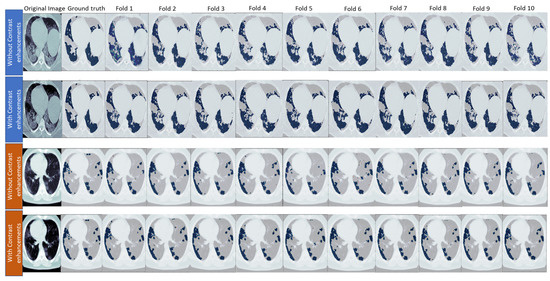

5.1. Preprocessing of MedSeg and Radiopaedia 9P Datasets

5.2. Preprocessing of Zenodo 20P Dataset

6.2. Binary Class Classification

6.3. Multi-Class Classification